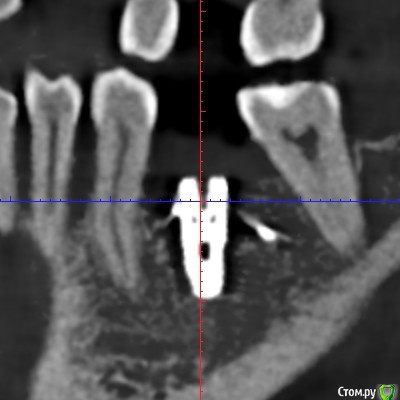

Делалась установка имплантов 5-6 месяцев назад. Скоро буду установлены формирователи десны, а потом временные коронки, с которыми ходить полгода. Для того, чтобы за это время свести к минимуму последующее обтачивание своих здоровых зубов при постановке постоянных коронок на импланты, ортопед отправил на консультацию к ортодонту, сказав, что можно попытаться если не полностью, то хотя бы с каким-то эффектом переместить сместившиеся зубы. Хирург в некотором роде поддержал, сказав, что использование временных коронок в качестве опоры для перемещения даст нагрузку на импланты и будет даже положительным фактором, если нагрузка не будет слишком большая.

Одна отнеслась к описанной ситуации совершенно спокойно, согласилась, что слишком большую нагрузку давать не надо, а потихоньку можно вполне успешно закрепить ортодонтическую конструкцию на временных коронках 24 и 26 для перемещения с помощью пружин зуба 25 к 24, а зуба 27 - от 26, туда, где они и были не так давно, перед имплантацией. По времени спрогнозировала порядка 3-4 месяцев. В отношении зуба 37 с отталкиванием от временной коронки на 36 тоже никаких возражений не было, только по времени могло быть немного дольше, так как кость плотнее.

Вторая категорически отвергла укрепление дуг брекетов на 24 и 26. Мотивировала это низкой плотностью кости на этом участке, при которой пострадают импланты. Сказала, что если перемещать конкретно два зуба 25 и 27, то она прикрепит конструкцию только к ним, и они будут отталкиваться друг от друга без участия временных коронок. Прогноз по сроку увеличился от 6 до 12 месяцев, причём ещё была озвучена вероятность выталкивания зуба 25 при перемещении в наружную сторону. По зубу 37 опора на временную коронку на импланте также была отвергнута и предложен вариант с перемещением при помощи вкрученного мини-импланта в кость за зубом.